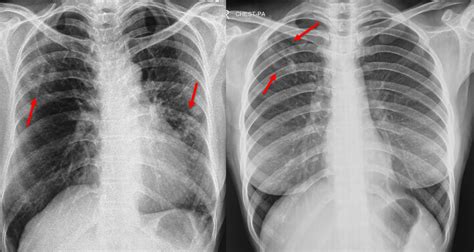

A chest X-ray is a diagnostic test that uses radiation to create images of the lungs and chest. It can help detect abnormalities such as masses, fluid in the lungs, or other changes due to TB. During a chest X-ray exam, the patient stands in front of an X-ray machine and takes a deep breath in while the image is being taken.

A chest X-ray is a non-invasive procedure that requires no injections or medication. It can quickly reveal evidence of TB and can identify changes in the lung tissue that suggest an active infection. In addition, it is relatively inexpensive and widely available. The chest X-ray is often used as a preliminary screening test for TB.

The chest X-ray cannot distinguish between active and latent TB infections. Furthermore, it can yield false negatives in patients who have early-stage TB, or whose immune system has not yet mounted a response to the TB infection. As a result, additional tests, such as sputum culture, may be required to confirm a diagnosis of TB.